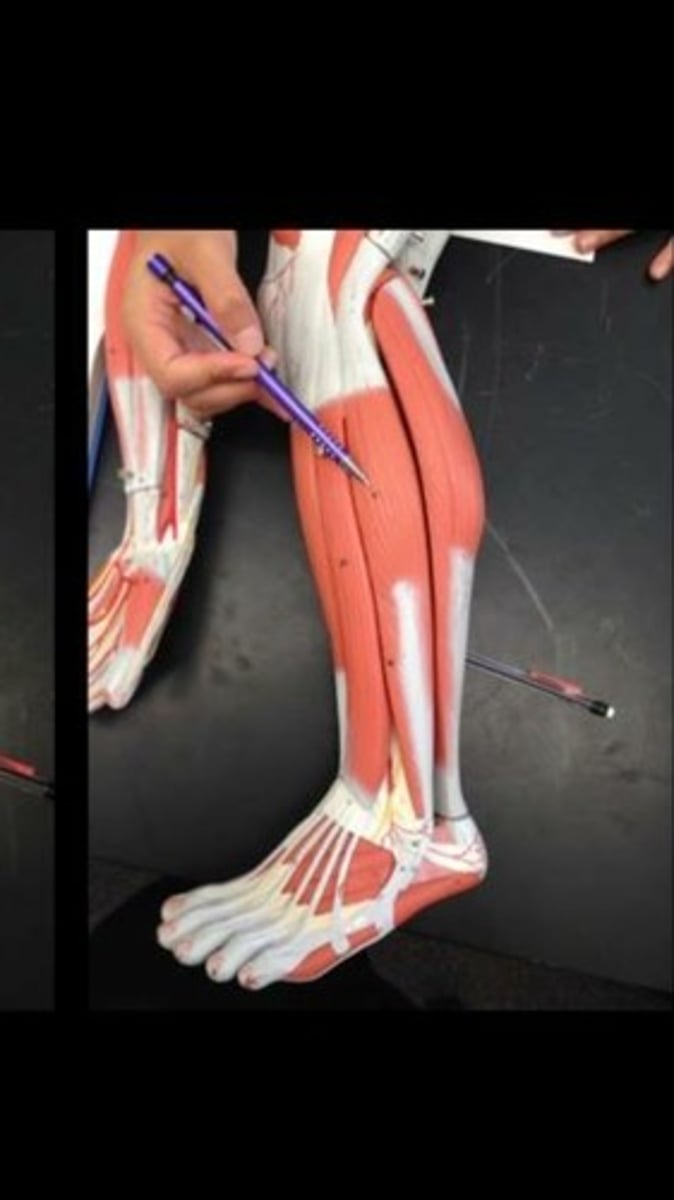

Tibialis anterior

Extensor digitorum longus

Fibularis longus

Soleus